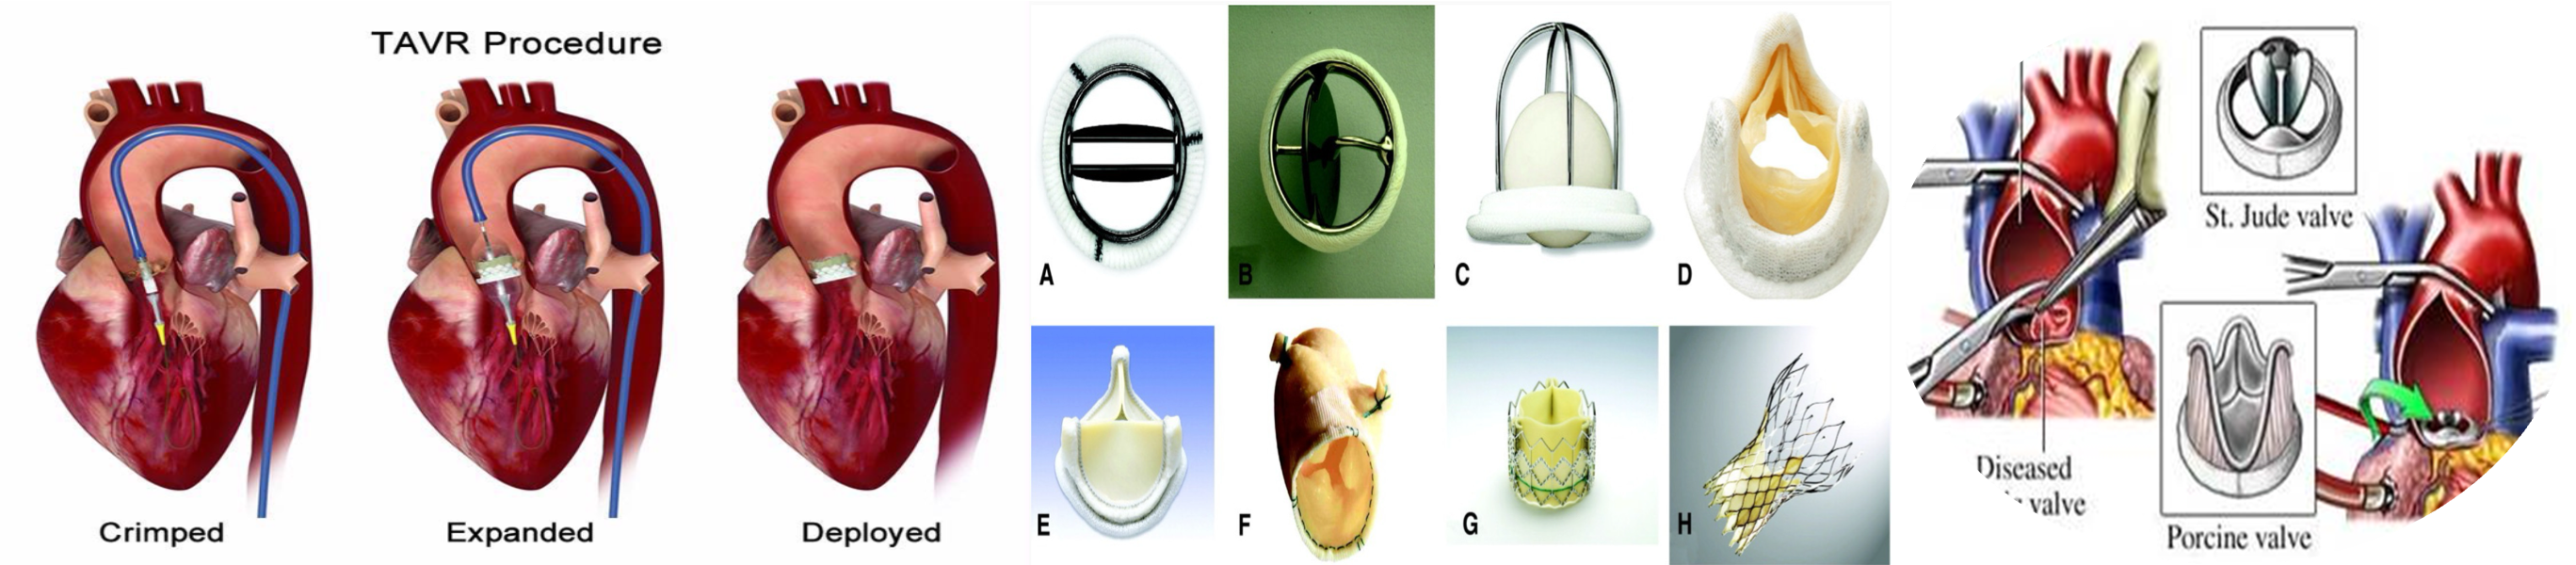

Symptomatic: Surgical therapy Aortic valve replacement (AVR): effective either with Bioprosthetic or Mechanical AVR Two approaches: 1. Surgical AVR: low surgical risk. 2. Transcatheter AVR: high surgical risk or contraindication

Aortic valve stenosis is a progressive condition, and definitive management requires valve replacement.

- Urgency of valve repair/replacement depends on staging.

- Symptomatic and/or severe AS: aortic valve replacement usually indicated.